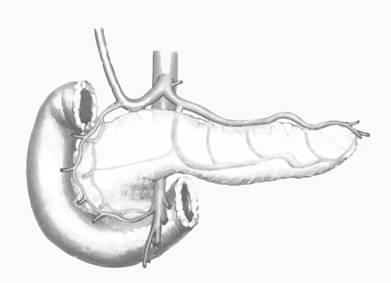

n панкреатоеюностомия:

а) продольная (Пестова-Джильсби)

б) терминальная (Дюваля)

n РЕЗЕКЦИИ PANCREAS

n КОРПОРОКАУДАЛЬНАЯ

n ПАНКРЕАТОДУОДЕНАЛЬНАЯ

n ПАНКРЕАТЭКТОМИЯ (ПРИМЕНЯЕТСЯ ПРИ ПРОДОЛЖИТЕЛЬНОМ БОЛЕВОМ СИНДРОМЕ И ПРИЗНАКАХ ОЗЛОКАЧЕСТВЛЕНИЯ ПРОЦЕССА)